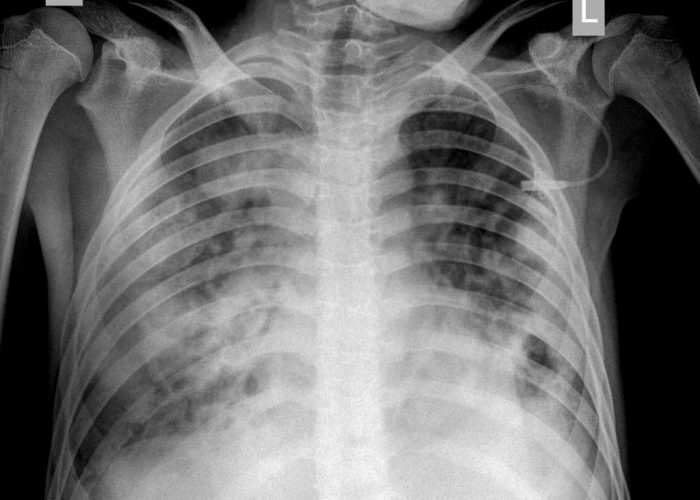

Рентгенодиагностика бронхопневмонии: Советы и примеры

Раздел: Альбом открытий